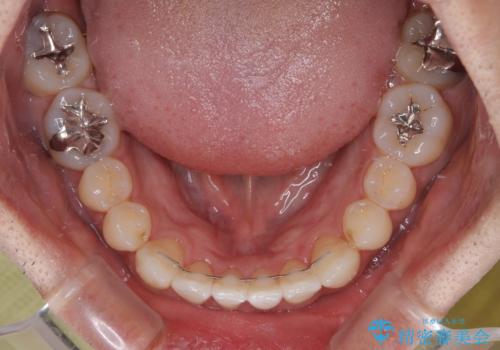

内側に引っ込んだ歯を治したい インビザラインの矯正治療

上下顎ともに歯列全体の側方拡大とIPR(歯と歯の間を削る)によってデコボコとクロスバイトが解消するように設計し、インビザラインにより治療を行うこととしました。

前歯の咬み合わせの調整などを行い、安定した咬み合わせに仕上げることができました。